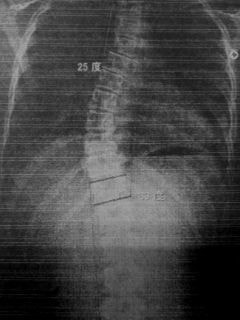

レントゲンのビフォーアフター)

写真1(施術前) 写真2(5か月後)

○コブ角上27度⇒25度(2度改善)、下40度⇒33度(7度改善)

※コブ角は専門医の診断

施術19回:コブ角33度

施術前:コブ角40度